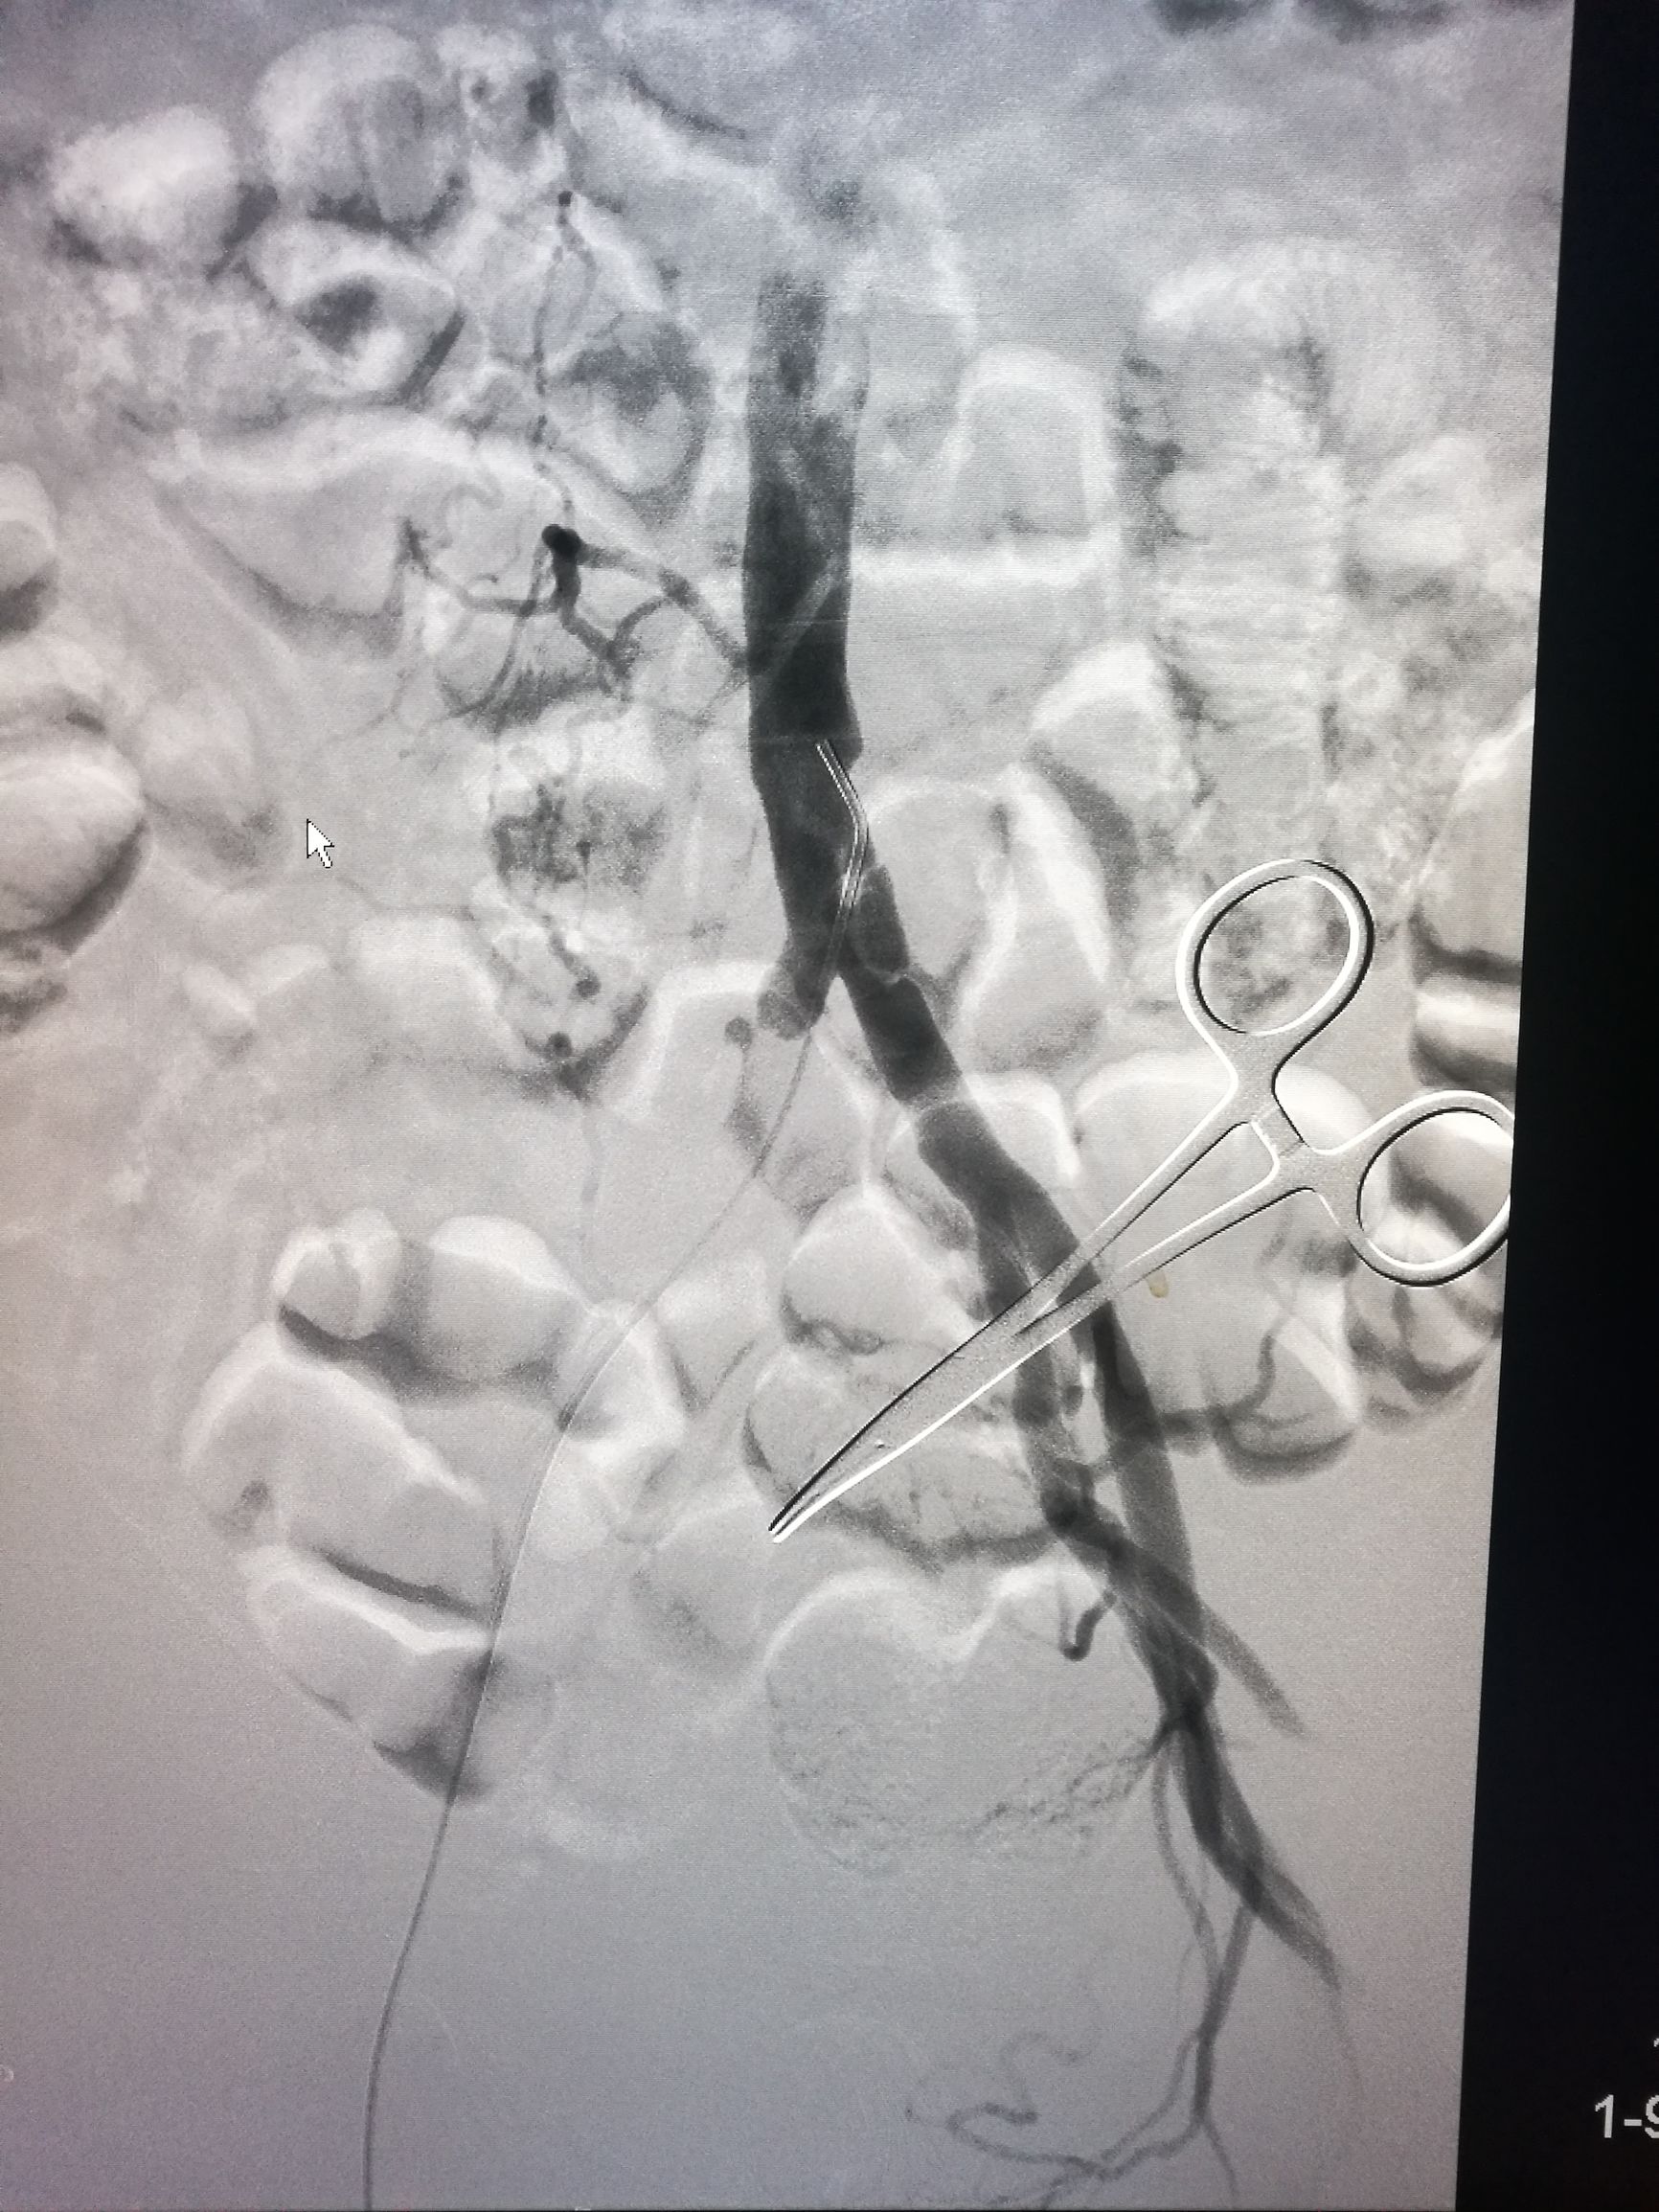

患者平卧位,常规消毒铺单,局麻下切开显露右侧股总动脉和股深动脉、股浅动脉。全身肝素化后,切开股动脉,对股浅动脉取栓后远侧回血好,对股深动脉反复取栓后出现汹涌回血。近端取栓后用导丝导管通过闭塞段到达腹主动脉下段,造影证实在真腔,用5*80mm球囊扩张后造影,髂动脉内有部分充盈缺损。植入巴德Fluency8*100和8*60覆膜支架后用7*60球囊扩张,造影管腔光滑(如图)。缝合动脉切口,关闭伤口,术毕。